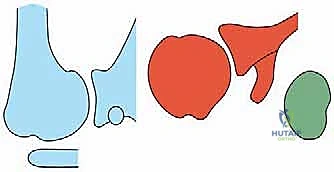

Computed Tomography (CT) scanning, preferably with advanced 3D reconstruction capabilities, is the current gold standard for quantifying glenoid version, assessing volumetric bone loss, and classifying the glenoid morphology according to the modified Walch classification system. Walch Type A represents a centered humeral head with concentric wear (A1 minor, A2 major central erosion). Type B denotes posterior subluxation (B1), posterior subluxation with biconcave posterior erosion (B2), or monoconcave posterior wear with severe retroversion (B3). Type C indicates profound glenoid hypoplasia with increased retroversion (>15 degrees) but without posterior subluxation. Type D represents anterior subluxation. Magnetic Resonance Imaging (MRI) is utilized selectively, primarily in patients with rheumatoid arthritis or those with clinical suspicion of a concomitant rotator cuff tear (e.g., profound weakness in external rotation or elevation), to confirm the structural integrity of the cuff prior to committing to an anatomic arthroplasty.